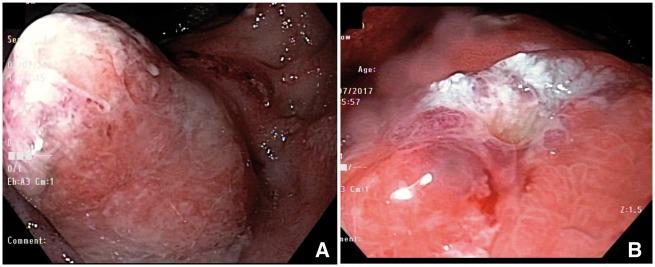

Restorative proctocolectomy with ileal pouch-anal anastomosis has become the surgical treatment of choice for patients with refractory ulcerative colitis, colitis-associated dysplasia or familial adenomatous polyposis. There are various pouch disorders and associated complications. Floppy pouch complex is defined as the presence of pouch prolapse, afferent limb syndrome, enterocele, redundant loop and folding pouch on pouchoscopy, gastrografin pouchogram or defecography. Common clinical presentation includes dyschezia, bloating, abdominal pain, straining or the sense of incomplete evacuation. Each disorder has its own unique endoscopic, radiographic and manometry findings. A range of therapeutic options are available for the management of the various causes of a pouch.

回肠袋肛管吻合术式的全直肠系膜切除术已成为难治性溃疡性结肠炎、结肠炎相关发育异常或家族性腺瘤性息肉病患者的首选手术治疗方式。存在多种袋状病变及相关并发症。松弛袋综合征的定义为在袋状内镜检查、泛影葡胺袋造影或排粪造影时出现袋脱垂、输入袢综合征、肠膨出、冗长肠袢及折叠袋。常见临床表现包括排便困难、腹胀、腹痛、用力排便或排便不尽感。每种病变都有其独特的内镜、影像学及测压表现。对于袋状病变的各种病因,有一系列治疗选择可供采用。